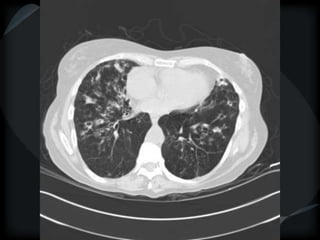

Airspace Patterns

 Diffuse ground-glass

 Patchy consolidation (peripheral)

 Inter and intralobular septal thickening / ground glass/crazy paving

 Alveolar sarcoid

Sarcoid- Hogshead cheese

Alveolar Sarcoid